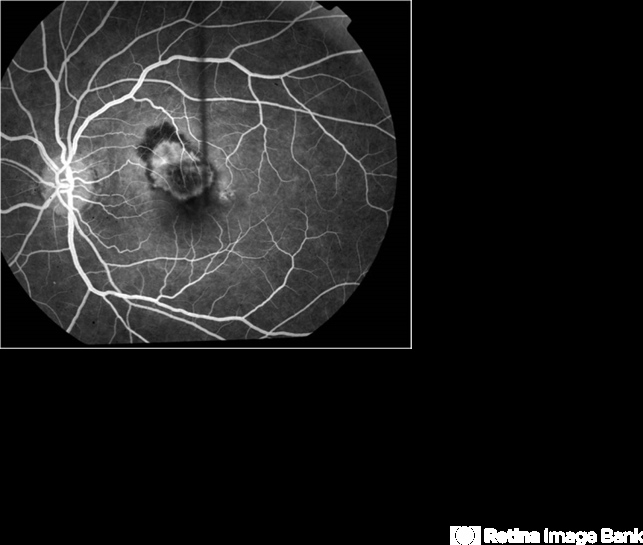

- macular hole, juxtafoveal choroidal neovascularization (CNV)

- Pt with full thickness macular hole complicated with CNV after macular hole surgery